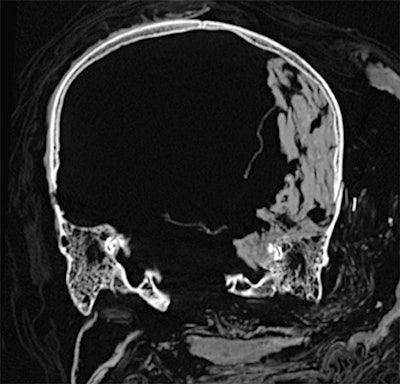

CT revealed details of the head injuries, including wounds that had not been discovered in previous examinations and had been skillfully hidden by the embalmers. The mummy's deformed hands indicate that Seqenenre may have been captured on the battlefield, and his hands were tied behind his back, preventing him from deflecting the fierce attack on his head.

The CT scans, combined with other evidence, suggest the execution was carried out by multiple attackers, which the scientists confirmed by studying five different Hyksos weapons that matched the king's wounds. The study also determined that Seqenenre was about 40 when he died, based on the detailed morphology revealed in the images, providing the most precise estimate to date, according to the authors.

In addition, the investigation revealed details about the mummification of Seqenenre's body. For instance, the embalmers used a sophisticated method to hide the king's head wounds under a layer of embalming material that functioned similarly to the fillers used in modern plastic surgery. This would imply that mummification took place in a real mummification laboratory rather than in a poorly equipped place, as previously interpreted.

Saleem examined the mummy on 4 May 2019. She said she used the usual optimum CT scan parameters, including field-of-view and slice thickness, to provide the best 3D reconstruction. Because of the COVID-19 pandemic, it took several weeks to study the Hyksos weapons stored at the Cairo Egyptian Museum and to correlate them with the injuries by physical inspection of the mummy and on CT scans.